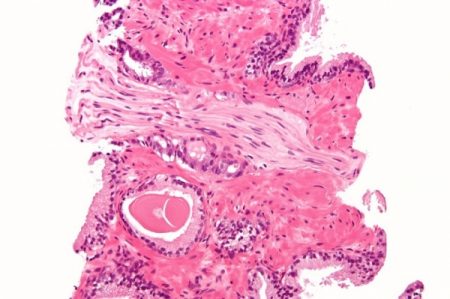

Prostate cancer is considered the most common form of cancer in men with it affecting 40,000 males annually and causes at least 10,000 deaths. One in eight men will come down with the disease in the span of their lifetime, with the huge majority of cases happening after the men turn age 65.

Most of the cancer cases are considered to be “slow growing” and medical supervision often recommends making sure to keep the disease under observation. Numerous males who suffer from the cancer will not suffer any harm from it, while treatment selections, such as chemotherapy, radiation and surgery can all cause severe side effects. Some of them include incontinence and erectile dysfunction.